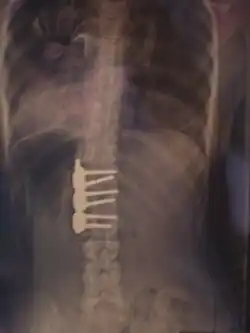

![]() Рентгеновский снимок позвоночника пациента со сколиозом с левосторонним искривлением в поясничном отделе и правосторонним искривлением в грудном отделе позвоночника. | |

Сколио́з (лат. scoliōsis ← греч. σκολιός «кривой») — трёхплоскостная деформация позвоночника у человека. Искривление может быть врождённым, посттравматическим и идиопатическим (т.е. "неизвестнопричинным").

Величина искривления позвоночника измеряется с помощью рентгеновского снимка всего позвоночника стоя. Возможны и врождённые рёберные деформации и деформации тел позвонков. С помощью этой информации можно отличить идиопатический и врождённый сколиоз. На рентгеновском снимке в боковой проекции можно также определить, есть ли врождённые деформации в этой плоскости или нарушения нормальных изгибов позвоночника — физиологических кифозов и лордозов.

Схема анализа рентгеновского снимка для определения угла искривления разработана в 50-х годах XX века американским ортопедом Дж. Коббом (англ. John Robert Cobb). Угол искривления, измеренный по рентгеновским снимкам теперь называется «углом по Коббу». Для определения угла деформации на передне-задней рентгенограмме проводят две линии, параллельных замыкательным пластинкам нейтральных позвонков. В точке пересечения этих линий или перпендикуляров к ним измеряют угол сколиоза.